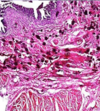

The mucosal glands are partly partly

ulcerated. The mucosa, submucosa, musculosa and serosa, show edema, congested capillaries and dense exudate formed of many pus cells and macrophages

Acute suppurative inflammation

Mucosal gland